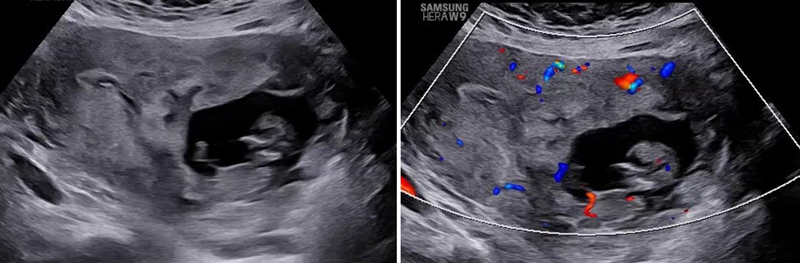

.png)

Hình ảnh trên siêu âm doppler cho thấy dấu hiệu cầu mạch máu và tăng sinh mạch máu mặt phân cách

Giai đoạn quý II, III, chẩn đoán NCRL không dựa vào một dấu hiệu đơn lẻ mà cần đánh giá tổng hợp các dấu hiệu siêu âm trên nền yếu tố nguy cơ. Hình ảnh thường gặp là:

- Xoang mạch máu trong nhau (Lacunae): bánh nhau có nhiều vùng phản âm trống/kém, bờ không đều với dòng chảy xoáy tốc độ cao trên 2D/Doppler. Phân biệt với xoang hồ huyết bình thường;

- Bất thường mặt phân cách nhau - tử cung: mất vùng phản âm kém sau nhau (Clear Zone), cơ tử cung mỏng <1mm, tăng sinh mạch máu trên Doppler màu;

- Bất thường mặt phân cách tử cung - bàng quang: cầu mạch máu, tăng sinh mạch máu giữa tử cung - bàng quang, thành bàng quang mất liên tục;

- Các marker khác: lồi nhau, chồi nhau, tăng sinh mạch máu ở cổ tử cung, dấu hiệu đường ray xe lửa, bánh nhau dày.